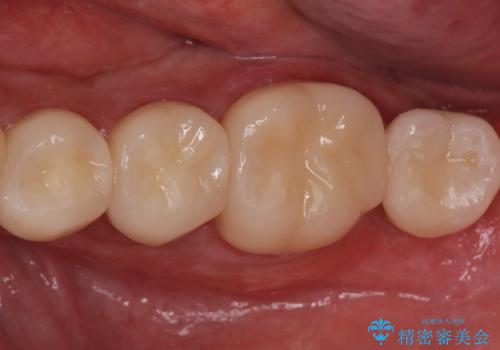

適合の良い被せ物、インプラントが入りました。